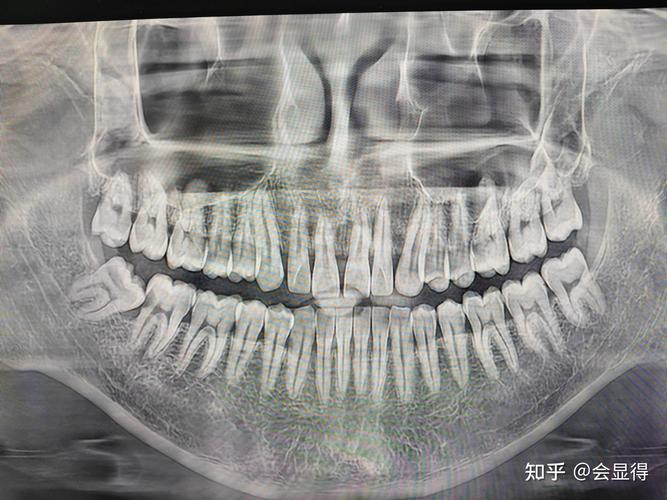

正畸前,医生通常会安排详细的口腔检查,包括临床检查和影像学检查,临床检查中,医生会通过视诊和触诊初步判断智齿区域是否有肿胀、牙龈红肿、萌出迹象或阻生情况,但临床检查存在盲区,尤其对于完全埋伏在颌骨内的智齿,无法准确判断其位置、方向与邻牙及周围结构的关系,全景片(曲面断层片)成为核心检查手段,全景片能清晰展示全口牙齿、牙根、牙槽骨以及颌骨内的发育情况,包括未萌出的智齿,通过全景片,医生可以明确智齿的数目、位置(如上颌或下颌)、萌出状态(正位、前倾、水平阻生、垂直阻生等)、牙根发育情况(是否形成)、与邻牙的距离(尤其是第二磨牙)以及是否压迫下颌神经管等重要解剖结构,若发现下颌智齿呈水平阻生,牙冠完全埋藏于下颌骨内,且牙根贴近下颌神经管,医生会将其标记为潜在风险因素,纳入正畸治疗方案的考量范畴。